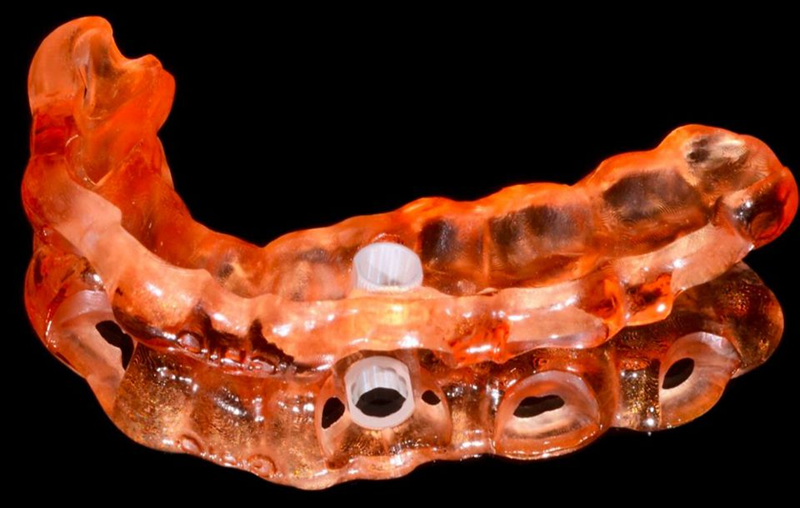

4.通过coDiagnostiX®计划生产印刷手术导板和树脂模型(图20-21)。

Fig. 20: In accordance with the STL file produced in coDiagnostiX®, the surgical guide was printed.

Fig. 21: The guide seated on the printed model to verify the precision of the procedure.